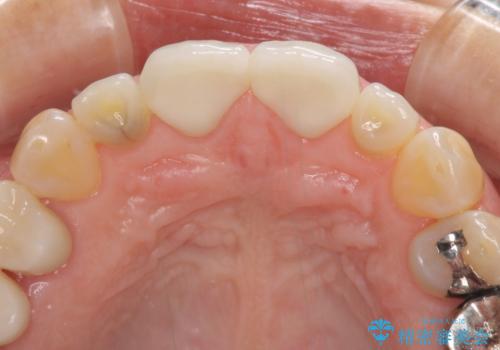

- 前歯のすきっぱを主訴にご来院された患者様です。他院でつめものやラミネートべニア(前歯の表面のみセラミックを貼り付ける)を行っていましたが、頻繁に外れることに悩まれており、クラウン(歯全体をセラミックがつつむ)をご希望されました。また、奥歯に大きな虫歯があり、歯が割れていたため、奥歯の治療も併せて行いました。

今回はまず欠けた場所を修復して見た目を回復させたのち、ラミネートべニアの仮歯をつくり、しばらく使用して考えて頂きました。メリットやデメリットを説明した結果、外れにくいセラミッククラウンをご選択頂きました。

咬み合わせや元のご自身の歯の色に特徴があったため、セラミッククラウンを修正したり、隣の歯を金属を外して白いつめものに変えたりして経過観察を長めに行いました。

患者様には大変満足して頂きました。